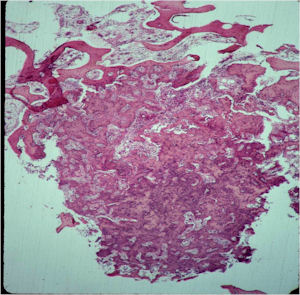

- The nidus of an osteoid osteoma consists of vascularized fibrovascular stroma and trabeculae of immature woven bone

- Nidus is sharply demarcated from surrounding reactive bone and there is an abrupt zone of transition between normal bone and the osteoid osteoma. There is no permeation of the lesion through the surrounding reactive trabeculae of bone,

- The trabeculae are uniformly lined by plump, uniform, active osteoblasts (“Osteoblastic Rimming)

- Mature nidus consists of more heavily calcified trabeculae of woven bone and osteoid